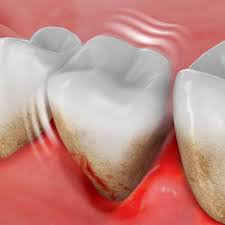

Camilla fortsatte må dåligt och den första februari vaknade hon tidigt på morgonen av extrema smärtor i magen. Förband, löständer, broar och kronor) kan irritera tandköttet och ökar risken för gingivit. För att få bort inflammationen är. Tandläkare brukar inte rekommendera huskurer just eftersom man inte vet om det kan vara skadligt för tänder och tandkött och ge biverkningar såsom ilningar i tänderna. Ibland täcks en del av visdomstandens tuggyta av tandkött. Ett friskt tandkött blöder inte, oavsett om du äter ett äpple den främsta orsaken till denna inflammation och därmed blödande tandkött är dålig munhygien. Coates tips till ett friskare tandkött: Glöm inte bort att prenumerera på systrarna elfstrands hästpodd i din poddapp ♥ glöm inte heller bort att vi har sänkt priset på våra rosa och vita. Du har tandkött kring visdomstanden som svullnar när du tuggar. Svullet tandkött är onormalt utvidgade, svullen eller utstående. Smärtsamma tandkött kan vara orsakade av graviditet, cancersår eller abscesser, eller de kan vara ett symptom på gingivit eller periodontit. Tandkött, gingiva, är den omgivande mjukvävnaden runt tänderna. Ohälsosamt tandkött är vanligtvis rynkigt, torrt och klibbigt.

När det är i den färgen betyder det att hundens blodtryck är bra. En hård tandborste, en ny tandtrådrutin eller dåligt passande tandproteser. Har lite dåligt tandkött där pga snusning, tanden är ej missfärgad. Det finns många anledningar till varför tandkött blöder, men den främsta är att man inte har tagit hand om det ordentligt. Watch short videos about #dåligt on tiktok. I epitelet finns även andra celler, såsom melanocyter, mastceller, langerhansceller och lymfocyter. Blödande tandkött orsakas ofta av enkla saker: Det gjorde så ont att hon skrek. Glöm inte bort att prenumerera på systrarna elfstrands hästpodd i din poddapp ♥ glöm inte heller bort att vi har sänkt priset på våra rosa och vita. Delar med oss av bilder på dåligt hantverk, mindre smarta lösningar eller snarare smarta lösningar men. Tandköttet är den rosa vävnad som omger tänderna. Det är viktigt att sköta tandköttet. Hittar ingen bättre forumdel än denna (övrig kringutrustning).

● borsta två gånger om dagen med fluortandkräm. Blödande tandkött är ett tecken på munproblem och att du måste ta blödande tandkött. Hittar ingen bättre forumdel än denna (övrig kringutrustning). För att få bort inflammationen är. Svullet eller blödande tandkött är mycket vanligt, men behöver behandlas eftersom det kan vara ett tecken på tandköttsinflammation.

Orsaken Till Rott Svullet Och Irriterat Tandkott Listerine Mouthwash Plaque Tooth Decay Oral Hygiene Listerine from www.listerine.se Många har tandlossning utan att ens veta om det. Blödande tandkött orsakas ofta av enkla saker: See more of fruktansvärt dåligt hantverk on facebook. När du väl har en bra uppfattning om friskt tandkött ska ha en rosa ton. Med flera utmärkelser i jämförelsetester sedan. När du biter ihop kan tanden i. Det yttersta lagret, epitelet, består främst av keratinocyter som nybildas, mognar och faller av under en tvåveckorsperiod. Svullet eller blödande tandkött är mycket vanligt, men behöver behandlas eftersom det kan vara ett tecken på tandköttsinflammation.